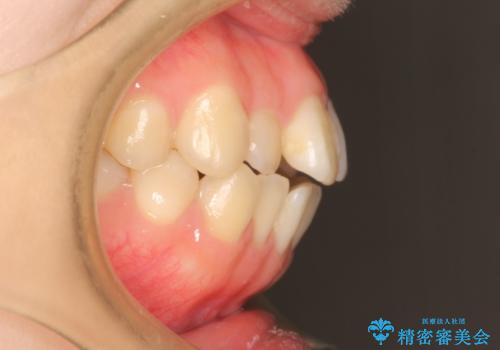

前歯にがたつきがあり、上下の歯が咬み合っていない状態でした。

歯列の横幅をひろげるのと、歯と歯の間をわずかに削ることにより、前歯のがたつきと、開咬を改善しました。